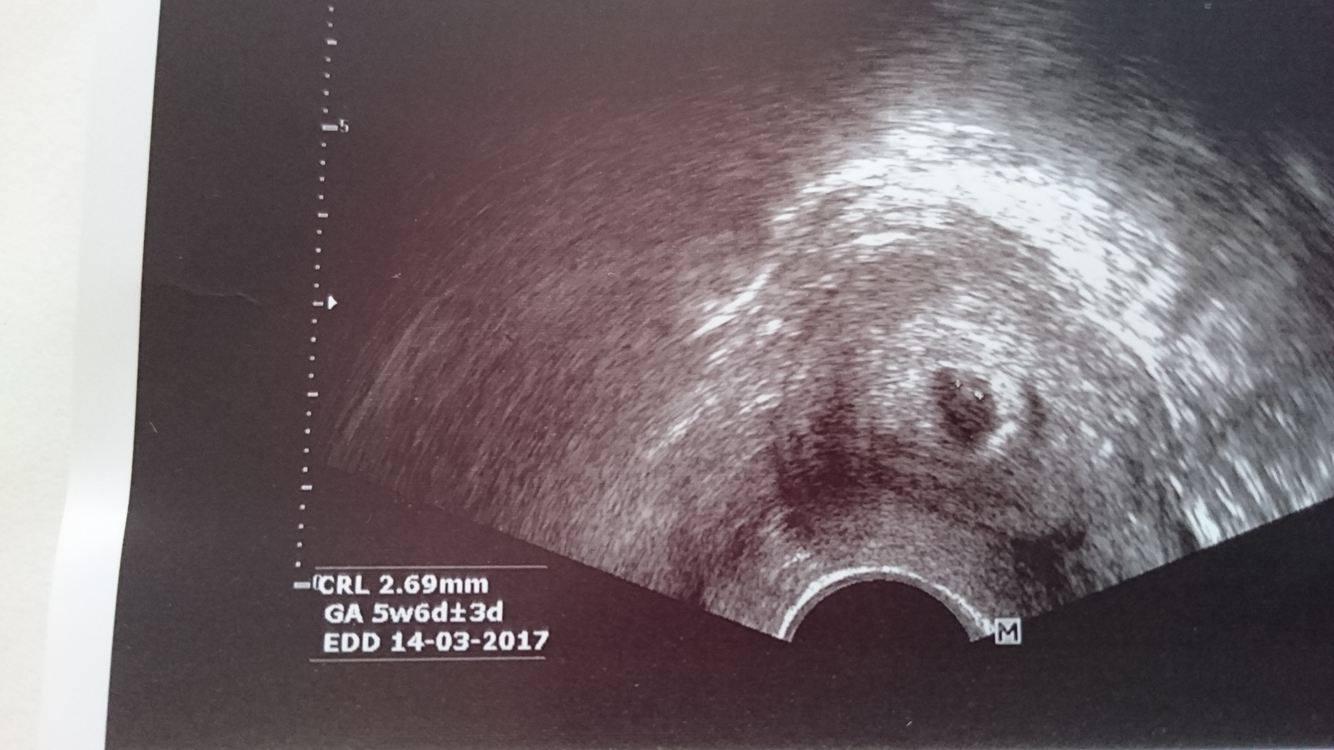

@juliemichal tak je to tam kde to ma byt podla utz to je 5+6 srdiečko este nemame ale do tydna by sa malo objavit ale my budeme pryč takze sa to dozviem az 1-4.8 na dalsej kontrole dufam ze bude buchat ako zvon to srdiečko uz 😀 mam radost inak hcg 14.7 1700 15.7.3000 a dneska 18.7- 8015 takze roste jak blázen 😀